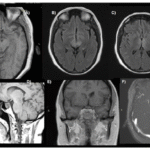

Osmotic demyelination syndrome (ODS) is a rare but significant complication associated with the rapid correction of hyponatremia. Pituitary necrosis, commonly observed in cases of apoplexy, may manifest in susceptible metabolic conditions but is infrequently documented in association with ODS.